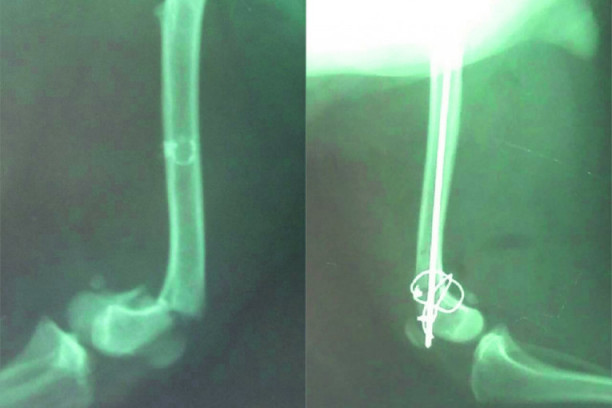

Foto: Saša Kosijer

- Prema manjim životinjama se treba ophoditi kao prema rotvajlerima - rekao je veterinar Kosijer, koji je za samo nekoliko nedelja zbog nemarnosti vlasnika obavio intervencije na maltezeru i mački sa slomljenim udovima.